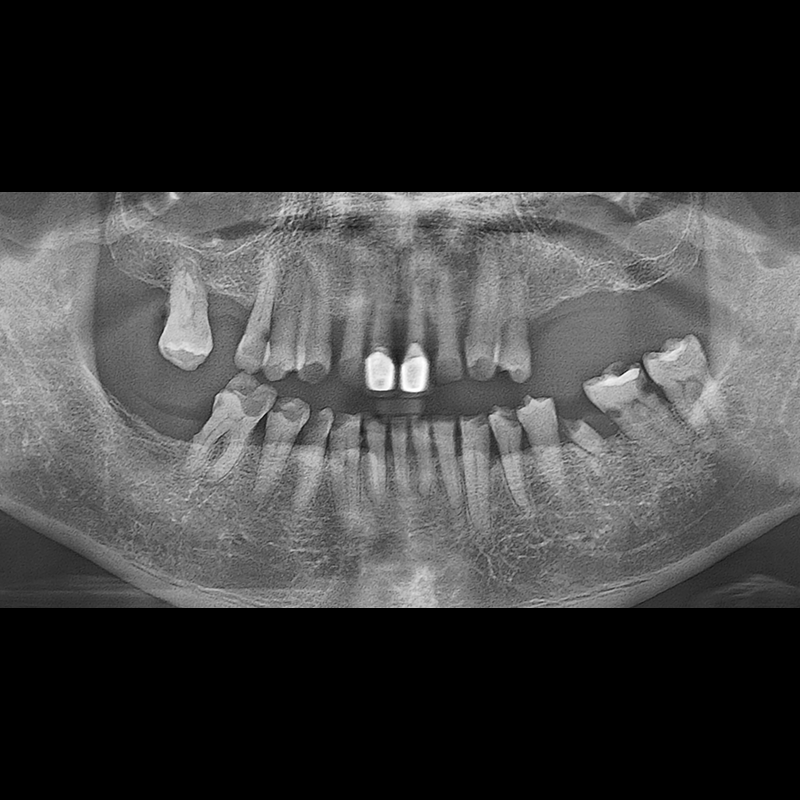

IMPLANT

BEFORE AFTER

임플란트 전후사진 2025.05.30

결손된 치아 부분과 살리기 힘든 치아 위치에 임플란트를 식립하였습니다.